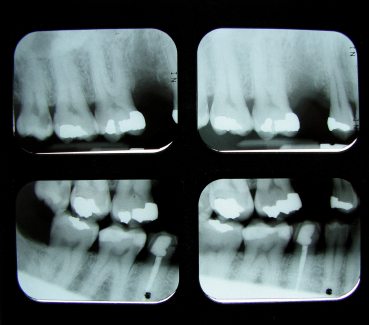

Dr. Beck & Dr. Morrow at South Waterfront Dental take great pride in providing state-of-the-art dental care to our patients. One of the most important